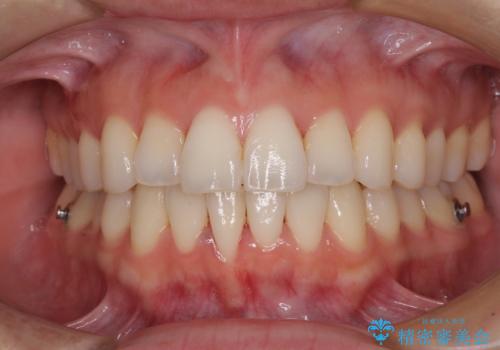

前歯のクロスバイト インビザラインによる矯正治療

- 上下のクロスバイトと前歯のデコボコを気にして来院された患者様です。

インビザラインを用い、IPR(歯と歯の間を削る)と歯列全体を拡大させることで、歯並びを整えていくこととしました。

治療を急いでいらっしゃらなかったため、のんびりと治療を進めていきました。3年以上の期間を要しましたが、きれいな口元に仕上がりました。